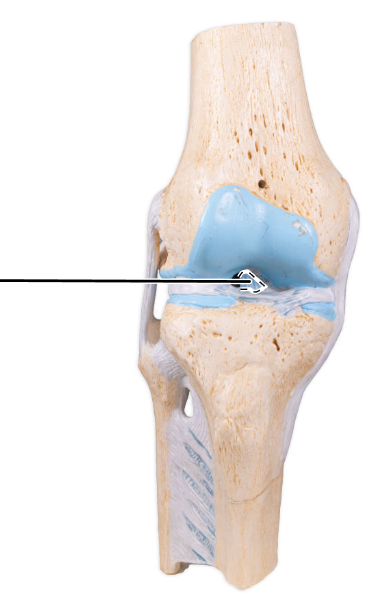

What ligament is shown here?

Anterior cruciate ligament.

What ligament is shown here?

Anterior cruciate ligament.

What does the anterior cruciate ligament prevent?

The anterior cruciate helps prevent anterior sliding of the tibia.

What ligament is shown here?

Posterior cruciate ligament.

What ligament is shown here?

Posterior cruciate ligament.

What does the posterior cruciate ligament prevent?

The posterior cruciate prevents forward sliding of the femur or backward displacement of the tibia.